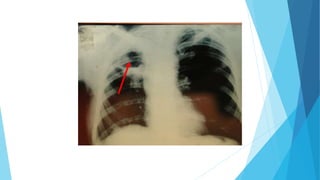

Imagenología

Lesiones infiltrativo

nodulares bilaterales a

predominio en los campos

pulmonares inferiores con

las características de

siembra hemática